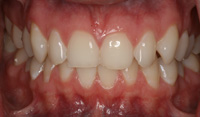

Lingual Veneers - Why? To restore worn-away enamel from acid erosion due to eating disorders.Lingual veneers are veneers that are placed on the inside, or lingual, surface of the front teeth. Rather than remove any healthy enamel from the remaining front and back sides of the teeth to do crowns, lingual veneers offer a conservative alternative for those who have experienced acid erosion, or tooth wear, of the lingual surfaces due to the detrimental effects of eating disorders such as bulimia. The goal is to build up and restore worn away teeth while preserving as much of the natural, beautiful and healthy tooth structure as possible. This strengthens and reinforces the tooth from further damage and drastically reduces sensitivity so a healthy diet and lifestyle can be resumed. Professional dental help for bulimia It is important to seek dental care if you have bulimia and to openly share with the dentist what is happening. Many dentists are caring professional people who understand the problems with bulimia and want to help. Without the dentist's help, the dental consequences of your bulimia can be severe. Dr. Berland can usually provide all of the dental services needed to restore the bulimic patient back to good dental health in a confidential and private manner. Additionally, Dr. Berland can help a bulimic patient manage the condition so that, even if they are continuing to have problems, the dental consequences of bulimia are lessened or eliminated. The Dallas Dental Arts services can be specially arranged for a bulimic patient so that all needed dental treatment can be intensively completed in a short period of time. This makes it possible for patients from out of town to complete their desperately needed dental care confidentially and in as few visits as possible. The Dallas Dental Arts can also assist in obtaining the funds for this care so everything that needs to be done can be completed. For more information on financial assistance, please click here. Dr. Berland has successfully cared for many patients suffering from bulimia and would be pleased to meet with you in a confidential consultation. Here, You can privately discuss your choices in dealing with your bulimia. Dr. Berland understands that you are struggling with bulimia and that it may take time to deal with the consequences of your bulimia. Privately speaking with Dr. Berland can be your first step in conquering your bulimia. Please consider calling (214)999-0110 and scheduling a consultation. You do not have to say why you are visiting, just that you would like a private consultation. If calling for an appointment is too embarrassing, you can first email Dr. Berland at drberland@dallasdentalspa.com or you can schedule a consultation and privately email him to let Dr. Berland know that you wish to talk about your bulimia. This young lady came to our office looking for a way to improve her smile, self-image and most importantly, her health. As a recovering bulimic patient, she had endured years of damage to her enamel from her previous history of eating disorders. In her case, the erosion wore all the way through her enamel and even into the soft, sensitive inner tooth layer, the dentin. She sought us out to find a way to restore her smile without further compromising the fragile condition of her teeth. Other dentists discussed filing her already thinned down teeth further and "strengthening" them with porcelain crowns. Our approach was completely different. Why take away more when you don’t have much to begin with? We recommended she try lingual resin veneers (on the backside of her teeth) followed by cosmetic one-stop bonding on the front and especially the edges of her teeth. This is a completely noninvasive and a purely additive procedure. She would be adding strength to her teeth, fortifying them rather than removing any of her remaining enamel, thereby reinforcing her teeth, improving her dental condition and creating the beautiful, yet natural, smile she desired. When the patient heard of this conservative treatment alternative, it made sense to her to preserve her teeth to maintain her health and restore her smile. Not only were the back sides of her teeth built out, length was added to replace what was worn over the years for a more youthful smile. After the no-shots, no-drilling, and no-pain appointment, her teeth were no longer sensitive to sweets, hot or cold. The patient was very pleased with her results. She not only gained a beautiful, new smile, but she also had a renewed confidence in herself and a reassurance of a healthier smile – and that means a healthier lifestyle as well! With all the focus of the media on diets, exercise equipment and personal care products, people are more concerned with their appearance and physical health than ever. In an effort to meet today's standard of beauty and "health", many people are quick to try the newest crash diet fad without ever realizing that this may, in fact, be the incorrect way to diet. These crash dieters who excessively fast, or try every new trend, tend to have a lack of, or decrease in certain vitamins, most notably Vitamins D, B-12 and calcium. They also tend to lack certain minerals and proteins in their diets. These are very important vitamins especially for the health of the teeth and gums. What can occur is that dieters tend to have a diet high in fruits which may contain a high content of natural sugars. These sugars tend to decay and erode the enamel of the teeth. Mints, used to combat the bad breath associated from Ketosis caused by an unbalanced protein diet and "so-called" Power Bars can further decay the teeth. Dieters also tend to take diet pills that may cause a decrease in saliva flow as a side effect. This decrease in saliva flow tends to increase the acid levels in the mouth which may cause an increased level of cavity formation. Antidepressants and decongestants have the same effect. Dr. Berland cares about the health and well-being of his patients. If you are currently on a diet that restricts certain food groups and/or you are taking a supplement or prescription diet aid, your oral health may compromised and in need of attention. Click here to see an example of the effects of eating disorders on your teeth. Please discuss with Dr. Berland at your next appointment any of these changes in diet or methods of weight control and any problems or discomfort you may be experiencing in your teeth and gums. Dr. Berland has many conservative measures to prevent and alleviate these conditions. Preventing a dental situation before it becomes a problem can save not only your teeth-- but, discomfort, time, money and your health. |